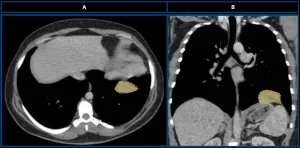

Chest computed tomography (CT) performed in the Netherlands

Axial (A) and coronal (B) CT scans (mediastinal window) demonstrate a solid, well-defined, homogeneous lesion with soft-tissue density (yellow dotted line) located at the base of the left hemithorax.